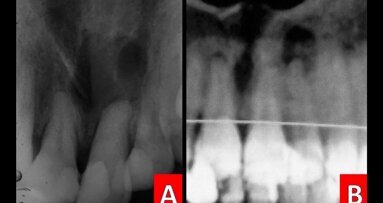

Caso 1 Paciente de sexo femenino de 12 años de edad que presenta diastema antero superior. A la palpación se oberva aumento de volumen en zona vestibular a nivel de línea media. Se toma rx panorámica y periapical, en la que se evidencia diente supernumerario mesiodens a nivel de piezas 11y 21.

Caso 2 Paciente de sexo femenino de 11 años de edad acude a consulta debido a la ausencia de la pieza 21, se observa giroversión de pieza 22. Al examen radiográfico se evidencia presencia de supernumerario y al examen de localización se encuentra en tabla ósea palatina.

Caso 3Paciente de sexo masculino de 9 años de edad. Al examen clínico se observa presencia de supernumerario entre piezas 11 y 21 y al examen radiográfico y examen de localización se evidencia la presencia de otro supernumerario en tabla ósea palatina.

Caso 4Paciente de sexo masculino de 9 años de edad con presencia de diente supernumerario intraóseo, evidenciado radiográficamente entre piezas 55 y 54.

Caso 5Paciente de sexo masculino de 9 años de edad acude a consultorio dental por tratamiento integral, al examen radiográfico se evidencia la presencia de un diente supernumerario a nivel de pieza 25.